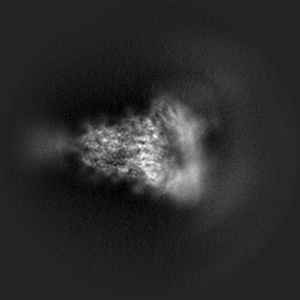

Trimer state of SARS-CoV Spike protein complexed with antibody PW5-535

Single-particle3.05 Å

Sample: SARS spike protein (S) in complex with broadly neutralizing antibody PW5-535